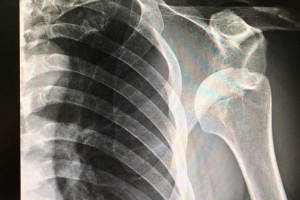

• How To Treat Shoulder Dislocations

How To Treat Shoulder Dislocations

Treatment for a shoulder dislocation typically involves the following steps: discuss at an appt with Dr. Catherine Logan